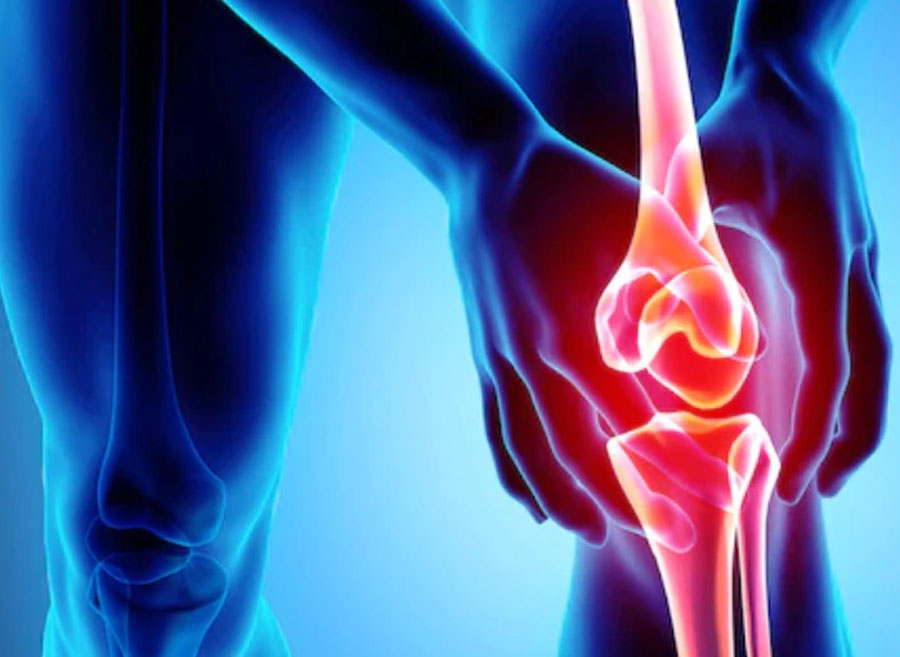

नई दिल्ली (एजेंसी)। अमेरिकन जर्नल ऑफ लाइफस्टाइल मेडिसिन में प्रकाशित एक नई रिसर्च के अनुसार, प्लांट-बेस्ड डाइट (पूरी तरह से शाकाहारी भोजन) का सेवन करने से रूमेटाइड अर्थराइटिस से जुड़े जोड़ों के दर्द को कम करने में मदद मिल सकती है। रूमेटाइड अर्थराइटिस एक ऑटोइम्यून बीमारी है जो मुख्य रूप से जोड़ों में सूजन, दर्द और जकड़न पैदा करती है।

रूमेटाइड अर्थराइटिस एक ऐसी ऑटोइम्यून कंडीशन है जिसमें शरीर का इम्यून सिस्टम गलती से अपने ही स्वस्थ ऊतकों पर हमला करना शुरू कर देता है। इस प्रतिक्रिया के कारण शरीर के विभिन्न अंगों में, विशेष रूप से जोड़ों में अत्यधिक सूजन और बाद में दर्द पैदा होता है।

अध्ययन के अंत में, शोधकर्ताओं ने पाया कि सामान्य आहार लेने वाले नियंत्रण समूह की तुलना में वीगन डाइट लेने वाले समूह के प्रतिभागियों में घुटनों के दर्द में महत्वपूर्ण कमी आई। इसके अतिरिक्त, वीगन आहार का सेवन करने वाले लोगों के घुटनों में सूजन की मात्रा भी कम हो गई थी।